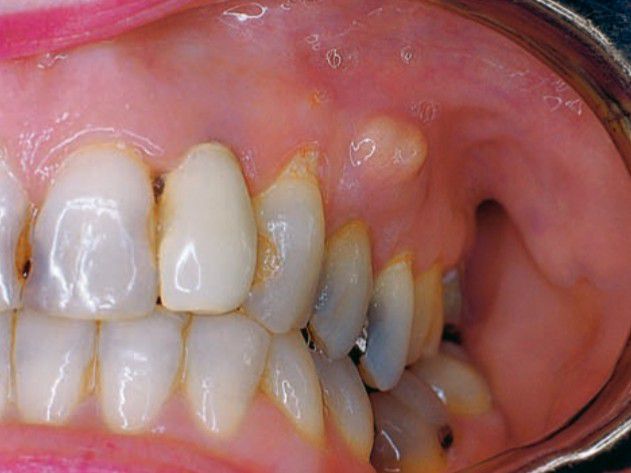

Gingival abscess

Parulis (gingival abscess) in maxillary mucosa and representing pus extension from a periapical abscess